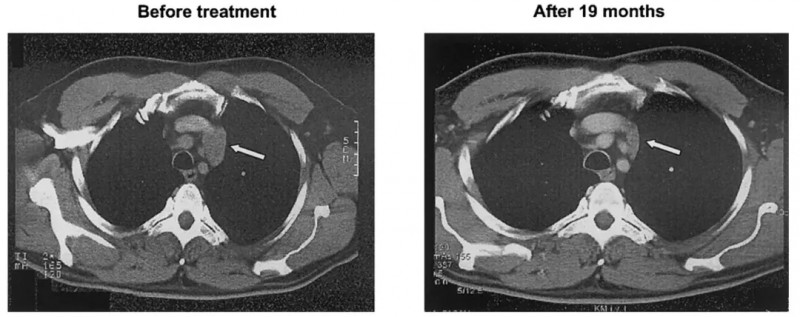

结果显示:治疗后CT检查显示,其皮肤转移灶及纵隔淋巴结消退(详见下图,箭头所示);除1个淋巴结略增大外,其余多数淋巴结无明显变化,且该增大淋巴结的病理活检提示纤维化,表明仅残留少量淋巴瘤细胞。此后患者肿瘤负荷稳步下降,经19个月持续治疗后最终达到部分缓解(PR)。

▲图源“Blood”,版权归原作者所有,如无意中侵犯了知识产权,请联系我们删除